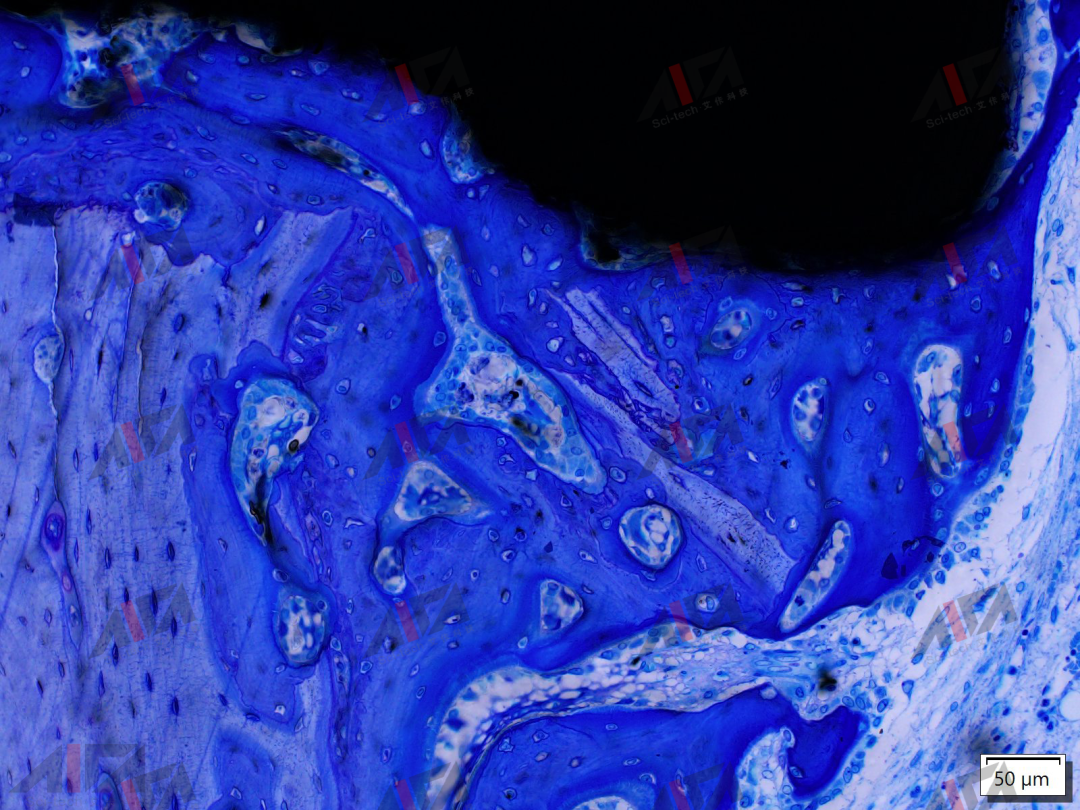

图片

硬组织切磨片 -甲-苯-胺蓝染色